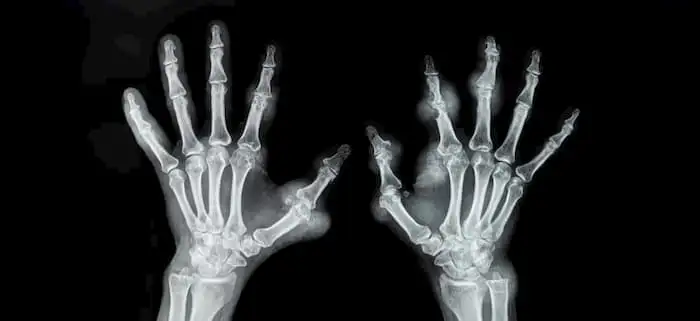

Do dietary choices affect risk of rheumatoid arthritis?

Rheumatoid arthritis Rheumatoid arthritis